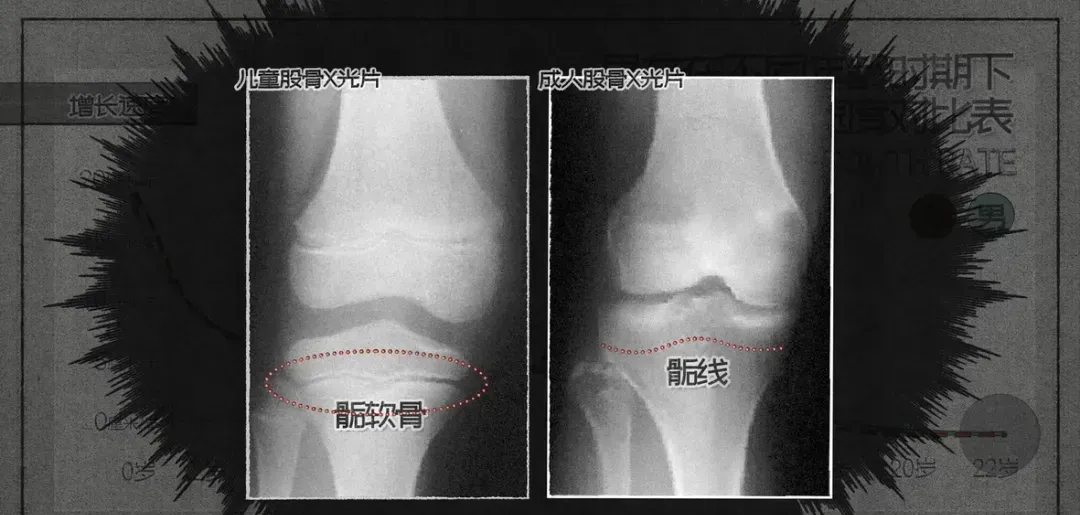

以大腿的股骨为例,从出生到成年期间,骨干部与两端之间始终保留着一定厚度的软骨层,称之为骺板或生长板。

这一软骨不断增殖和骨化,使得骨头得以延长,从而使个体逐渐长高。

随着骺软骨逐渐闭合,转变为薄薄的骨组织,进一步的软骨将不再增加,骨头因此停止了延长。

当所有骨骼完全不再增长时,身高也将停止上升。